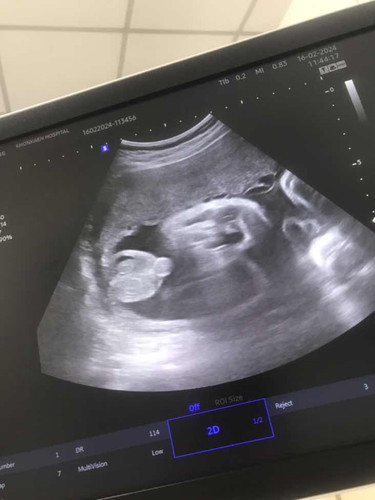

แม่ๆมาทายกันค่ะ ว่าจะเป็นผู้ชายหรือผู้หญิง ซาวมา8เดือนหมอบอกว่าเป็นผู้หญิง 99% ตอนนี้38วีคบอกเป็นผู้ชาย เซอร์ไพรส์เดือนสุดท้าย😂

มีโอกาสเป็นผู้หญิงมั้ยคะ เตรียมของไว้มีแต่ของผญ

คลอดแล้วค่ะแม่ ผู้ชายจริงๆด้วย แฮร่5555